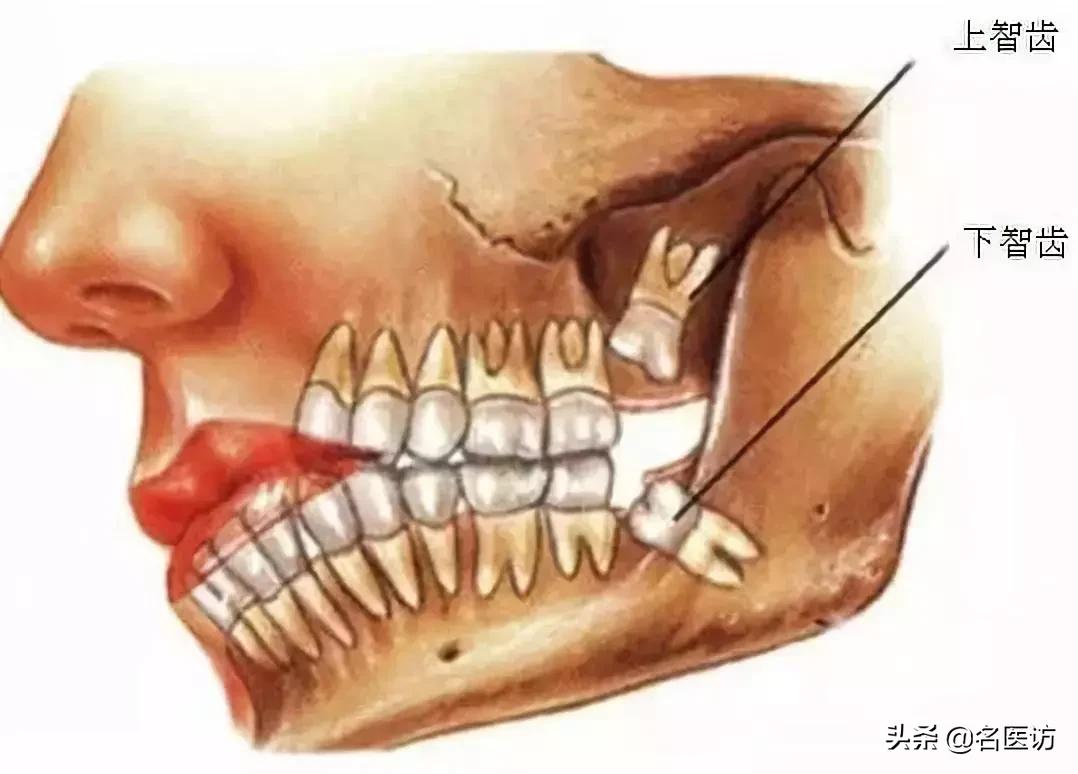

原来,智齿,学名叫第三磨牙,通常在人 17~25 岁时出现在口腔中。大部分人有 4 个智齿(上颌 2 个,下颌 2 个),但是也有人可能只有 1~3 个甚至没有。

当这些智齿突破牙龈,它们便被称为“萌出”。如果智齿不能萌出,或只能部分萌出牙龈,就叫做“阻生”。